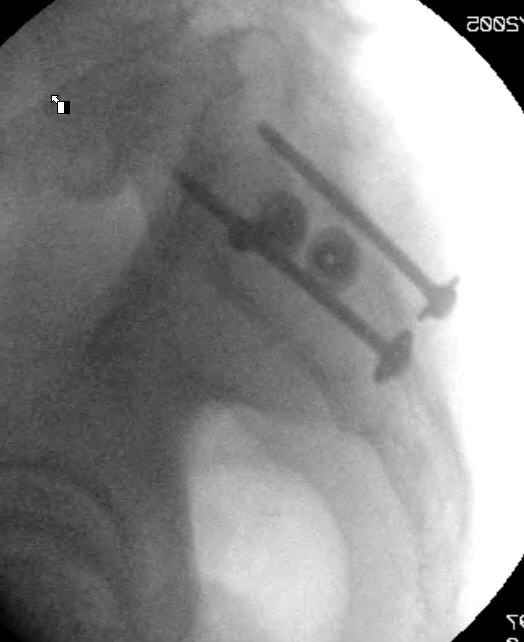

Hello gentlemen- Case is 52 YO male, fell out of treestand while deerhunting. He is 6 ft, approx. 260-275 lbs. Was hemodynamic unstable at local ER, sent to our Trauma center where circumferential pelvic binder placed and pt. stabilized with fluid, blood, and rewarming. Angiography not performed. An extraperitoneal bladder disruption was found, uro elected to treat non-operatively. Initial xray (not shown) demonstrated 5-7 cm wide at symphysis and SI joint. The first image attached is of CT once binder is in place. On post trauma day 5 the pt was taken to OR for ORIF of his iliac wing fracture and SI dislocation. The swelling/3rd spacing of fluid in the area of symphysis was profound, but quite acceptable posteriorly. Patient was prone for procedure, as I thought too difficult to fix the wing in lateral position. Of course the repair of wing was easy, but reduction of SI very demanding. The Floro images document the residual lack of reduction. That was the closest I could get it using 6mm joystick in wing, and clamp on sacrum and clamp through notch. The fixation was (initially) rigid. Anterior ex fix with supra-acetabular pins was placed due to condition of soft tissues, massive "beer-belly" overhanging the crest. Post trauma day ten patient's xray shows failure of posterior construct. Plan was to perform revision orif once soft tissues resolve considerably for full anrterior fixation and posterior fixation. However, while Im away for holiday (on Post trauma day 15), pt is developing septic clinical appearance, and trauma suspects pelvic abcess near symphysis and performs I and D - finds nothing but no primary closure performed. Posterior tissues/incision continue to look healthy. Now is post trauma day 17, pt is still tubed/on dopamine/and wbc still elevated, anterior incision still packed open. Clearly must get to bottom of possible sepsis, but then what? Thanks for you time - sorry for such lengthy clinical description. Thomas Schaller Kalamazoo, Michigan

5. Your caudal iliosacral screw is/was in his spinal canal... it's low and posterior and the lateral fluoro image confirms this... a postop CT will show it (or it's trail at this point)... canal screws do not hold.